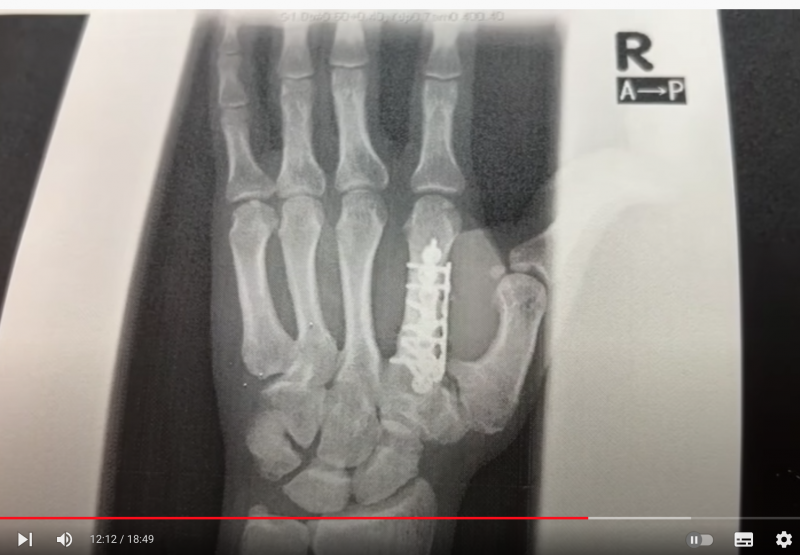

手術後のレントゲン写真。手の甲が真っ直ぐになった。手術した部分には金属プレートと15本のボルトが入った手術前、右手が開かない状態を説明(KAI Channelより)